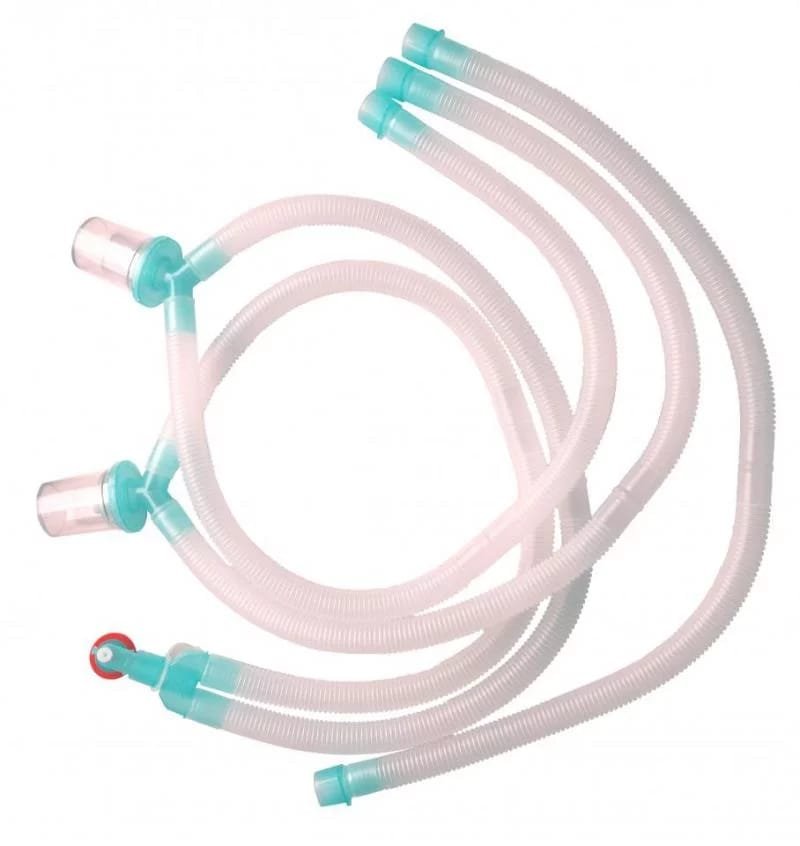

Bains Circuit

Bains CircuitOur ProductsFrom SurgicaveUplode:9 months ago from India